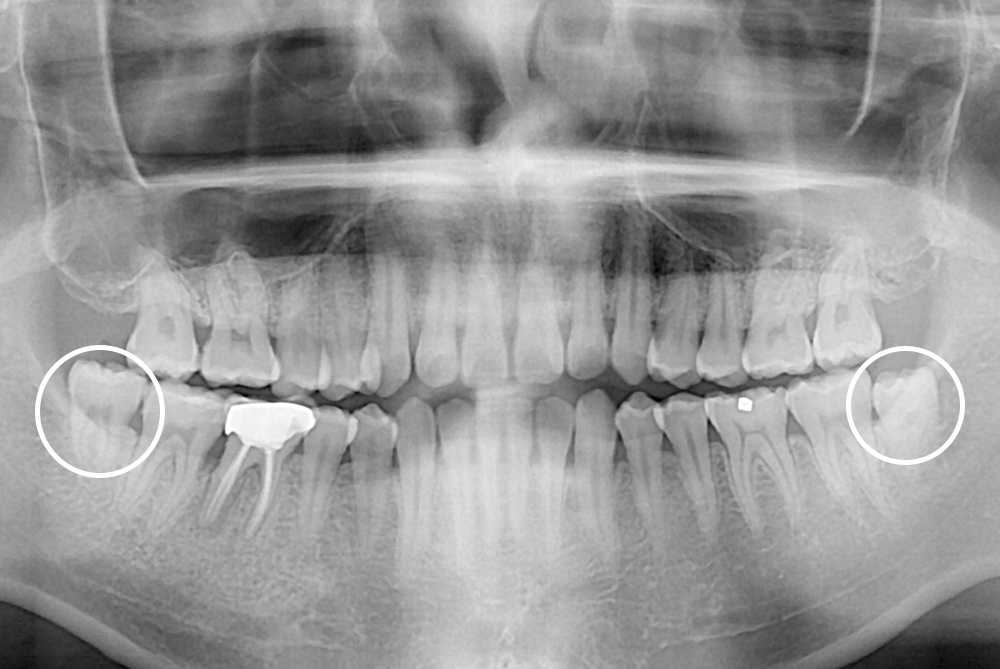

[사랑니] 매복 사랑니 발치

치료전 : 2017-07-10